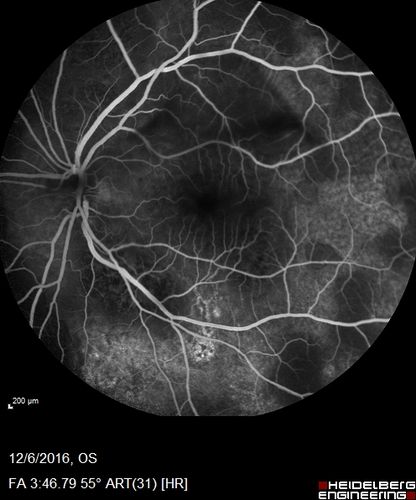

Ocular Lymphoma - non-Hodgkins - B-Cell

Multifocal sub-RPE lesions in the left eye of a patient with history of Non-hodgkins B-cell Lymphoma last active 2 years ago